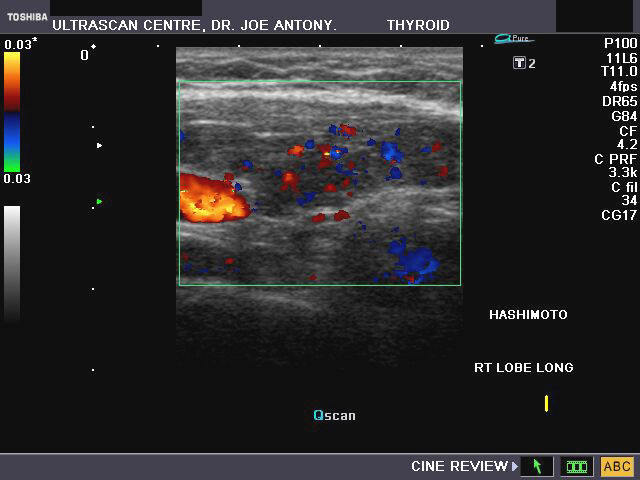

Hashimoto's thyroiditis

Sonography of the thyroid gland in this middle aged female patient reveal: 1) hypoechoic thyroid gland 2) coarse echotexture of the gland 3) fine linear echoes within the thyroid parenchyma s/o fibrosis 4) Color doppler imaging reveals augmentation of the vascularity of the thyroid gland. These ultrasound images are diagnostic of Hashimoto's thyroiditis. Images taken using a Toshiba Nemio- XG color doppler machine. Hashimoto's thyroiditis is often a cause of decreased thyroid function or hypothyroidism and is thus a causative factor in the development of obesity. Both type1 and type 2 diabetes may be associated with Hashimoto's thyroiditis.